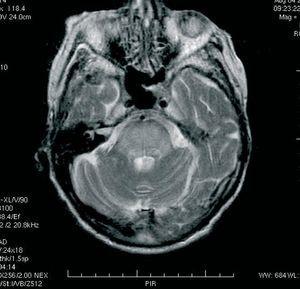

Mujer de 82 años en hemodiálisis desde hace 6 meses por insuficiencia renal crónica (IRC) secundaria a amiloidosis, que ingresa en situación de insuficiencia cardíaca. Se le realiza diálisis de urgencia con ultrafiltración de 2.500 y en el curso de 24 horas, una nueva ultrafiltración de 2.000 ante la escasa mejoría clínica y radiológica inicial. La paciente, que inicialmente presentaba un estado neurológico estable, inicia un extraño cuadro clínico al finalizar la segunda sesión aguda de diálisis, consistente en bajo y oscilante nivel de conciencia, ausencia de lenguaje, mirada inmóvil hacia adelante, con pérdida de fuerza en el miembro superior derecho y en los miembros inferiores. La evaluación especializada indica un proceso de desequilibrio en diálisis. Los niveles de Na prehemodiálisis y posthemodiálisis no presentaron alteraciones significativas (136 a 132 mEq/l) ni tampoco los cambios en el resto de parámetros (urea, etc.) se manifestaron fuera de lo esperable. Se realizó una TC craneal en la que se detectó un infarto lacunar talámico antiguo y una atrofia corticosubcortical. En la RM se objetivó una imhiperintensidad de toda la protuberancia y de la unión ponto-mesoencefálica sin restricción de difusión y, por tanto, no relacionable con isquemia, por lo que se indicó el diagnóstico de mielinólisis centroprotuberancial. Supratentorialmente, presentaba una importante hiperintensidad de sustancia blanca periventricular y algún infarto lacunar antiguo (figura 1).

Figura 1. Resonancia magnética craneal.